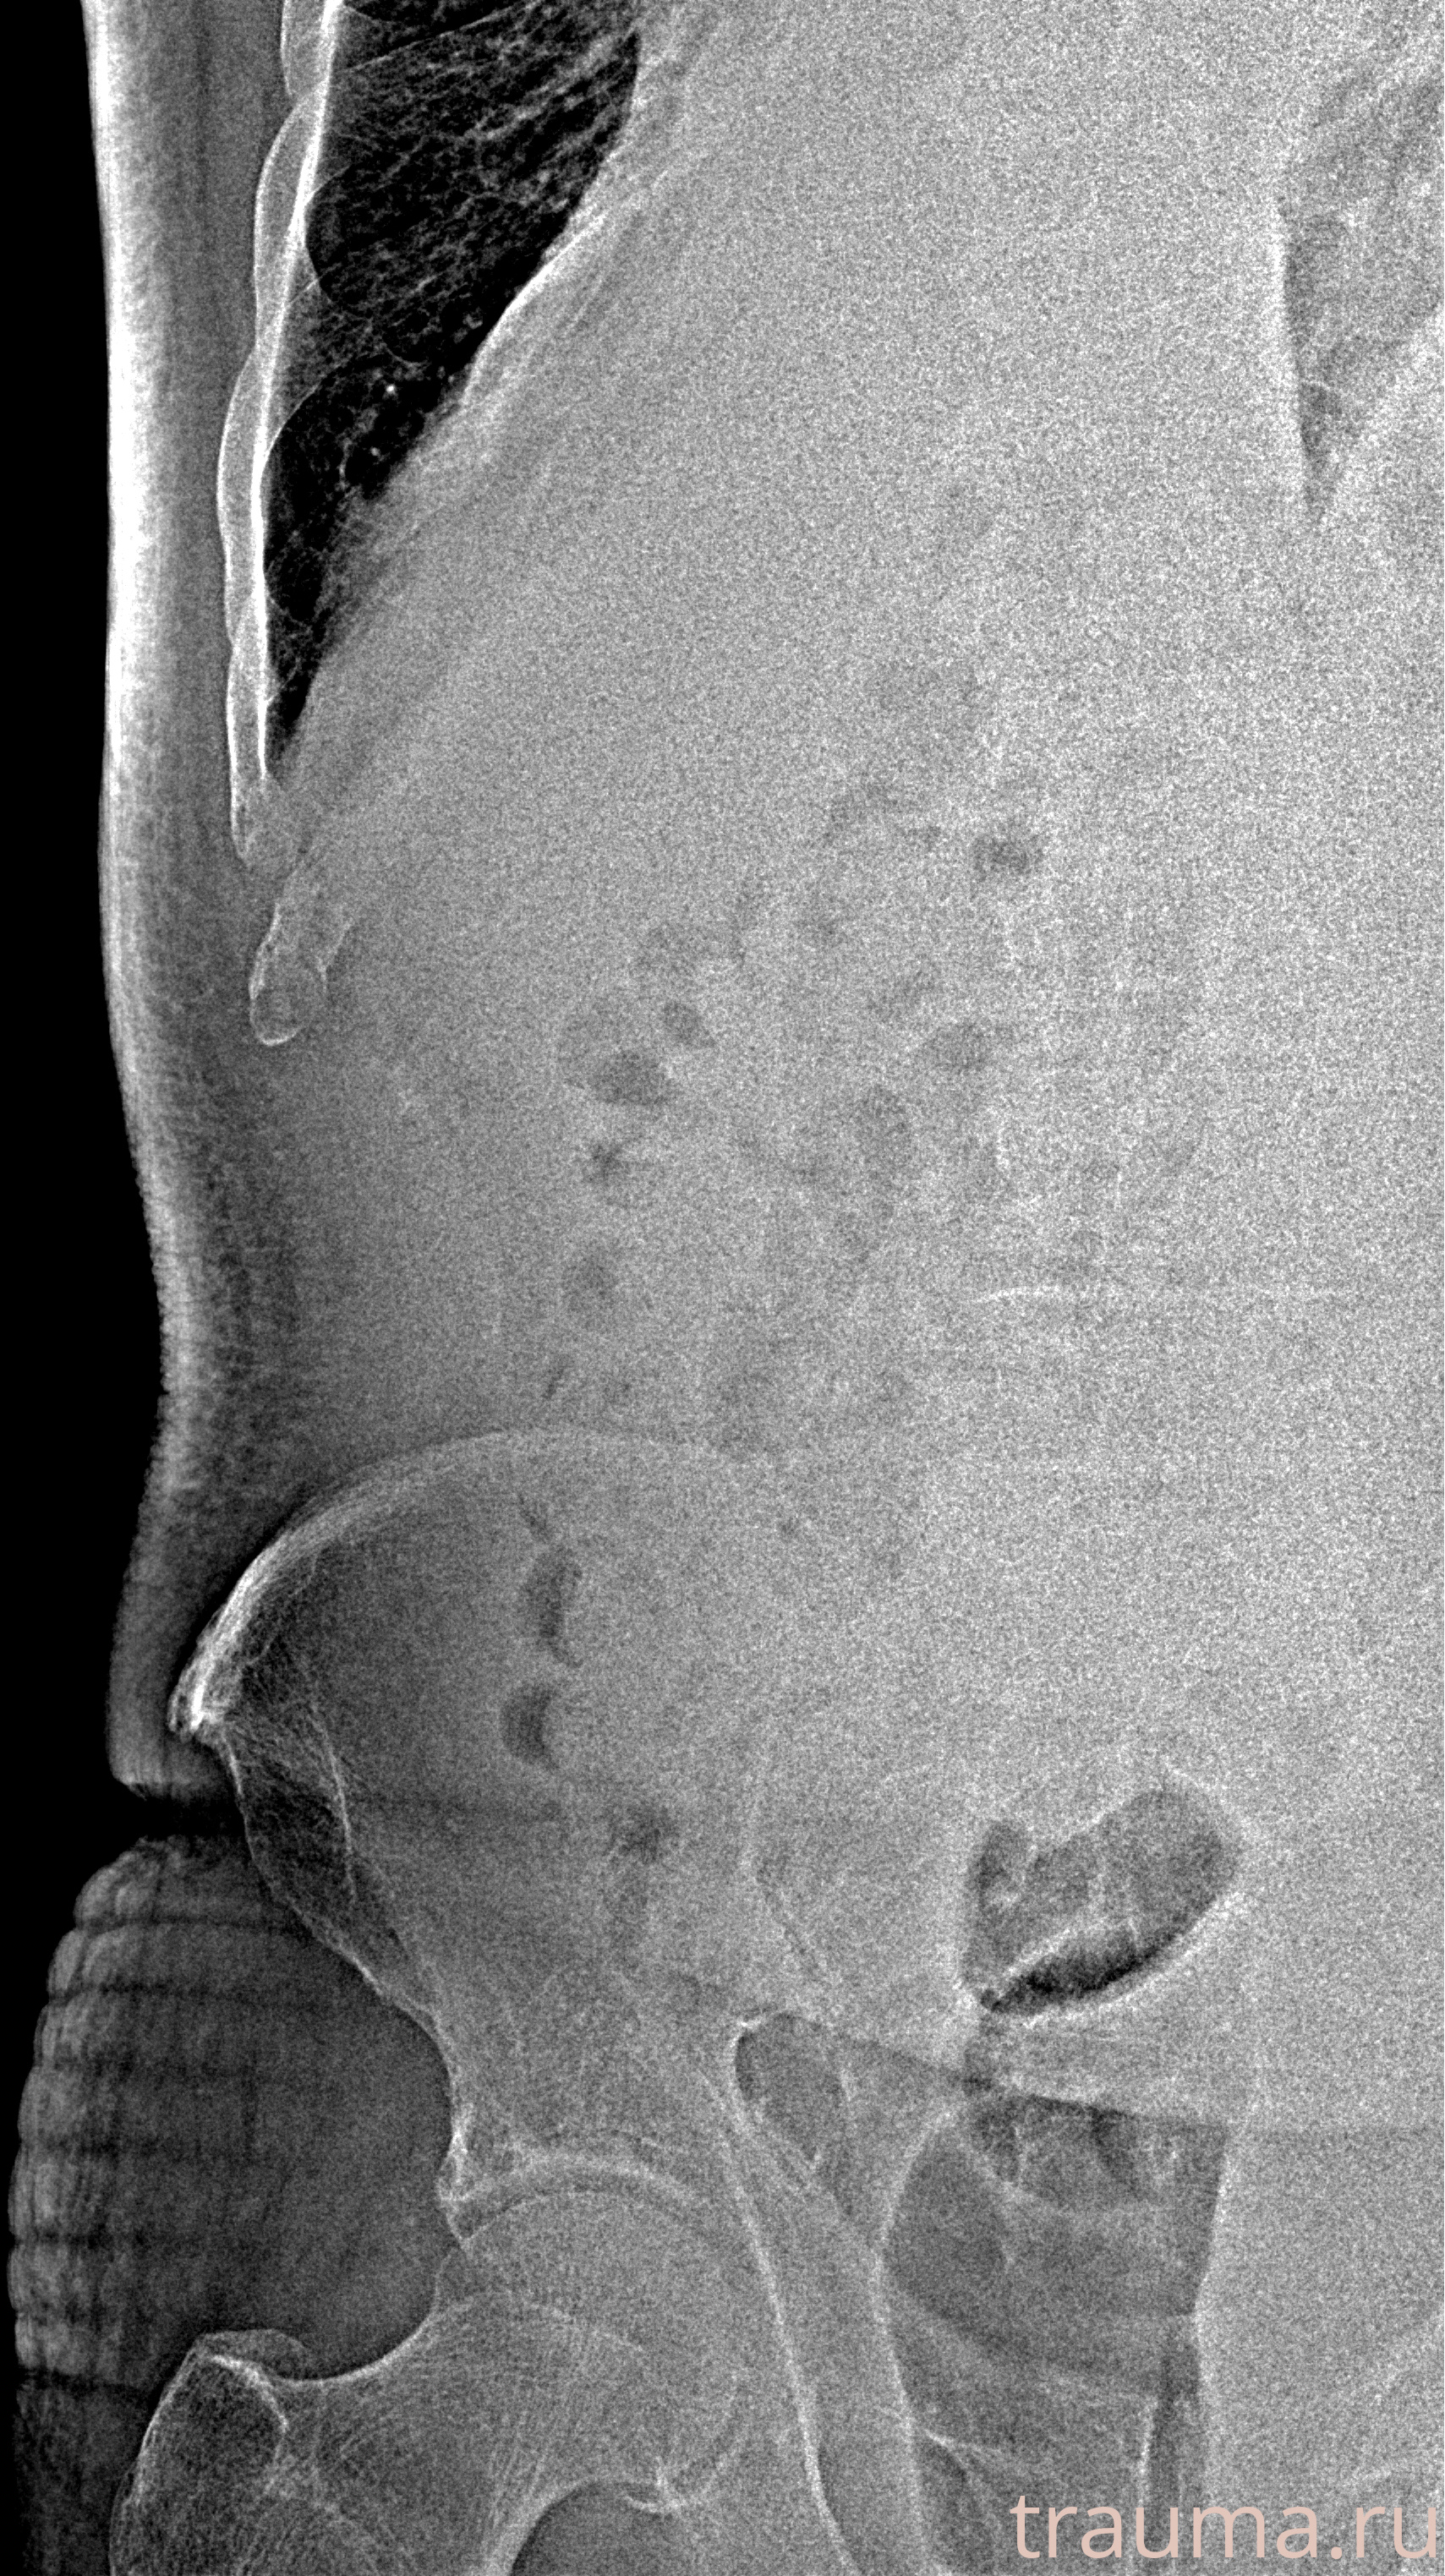

Рентген на дому: по вашему адресу приезжает врач-рентгенолог, травматолог-ортопед с мобильным рентгеновским аппаратом, проводит диагностику травмы или заболевания, делает необходимые рентгенограммы, дает рекомендации по дальнейшему лечению. Получить качественные снимки в домашних условиях возможно благодаря уникальной методике, разработанной МосРентген Центром для института  Склифосовского